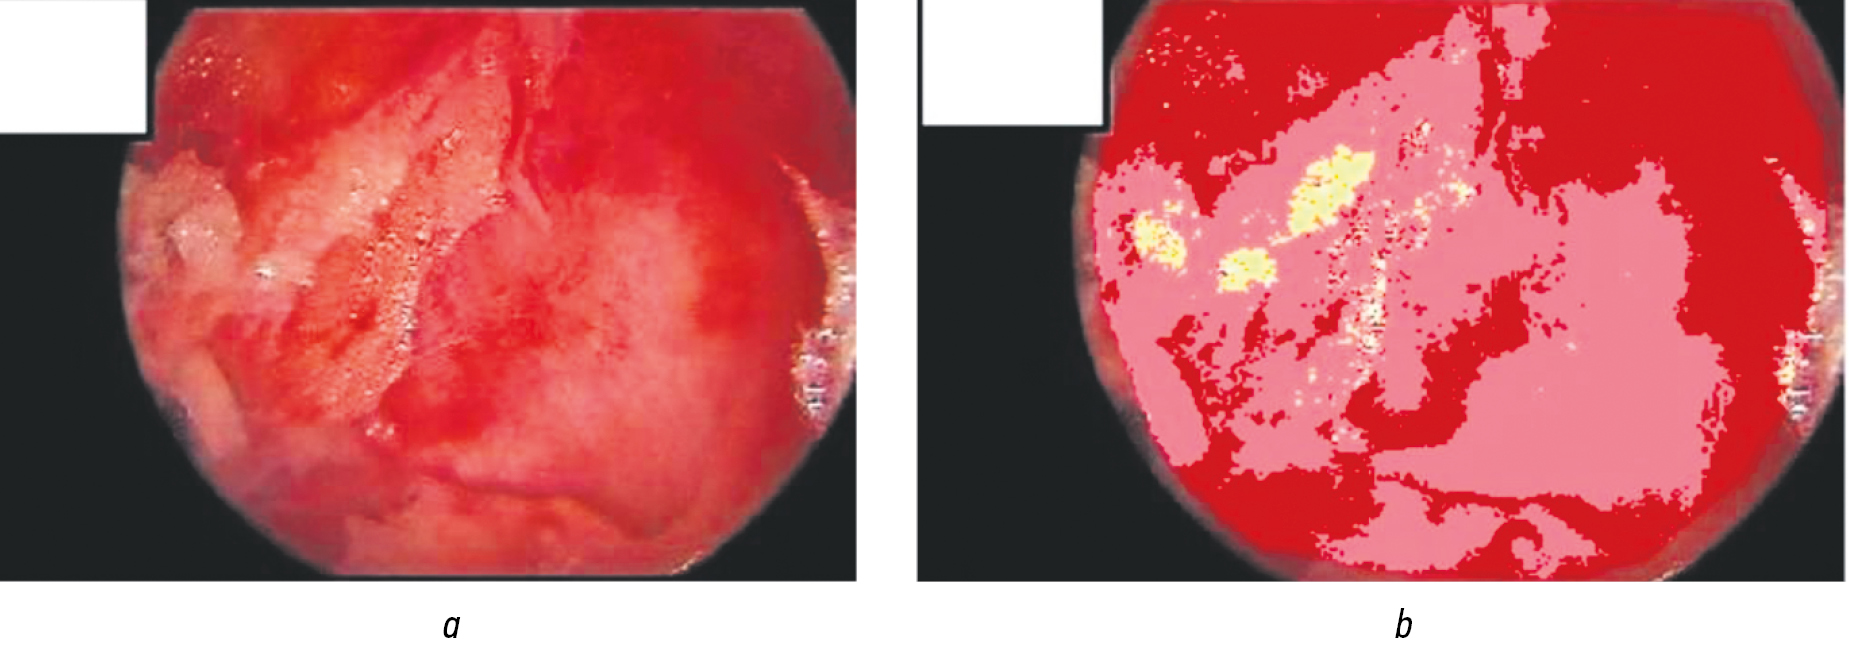

Результаты: фибрин — 6,1 мм2 (65,25 %); интактные ткани — 2,46 мм2 (26,32 %); некроз — 0,0 мм2 (0,01 %); грануляции — 0,24 мм2 (2,59 %)

В каждой ране выполнялась эндоскопическая фотофиксация в 3-х отдельных участках. Полученный результат анализировали с помощью программы «АналиРан». Производился расчет площади некроза, фибрина, грануляционной ткани и эпителия. Программа отображала вышеперечисленные характеристики в цветовом и цифровом форматах. Из всех ключевых показателей компьютерной планиметрии ран (площадей некрозa, фибрина, грануляционной ткани) наибольшую динамику показали относительные показатели грануляций, фибрина (рис. 7, 8).

Рис. 7. Компьютерная планиметрия при эндоскопии (первичная операция). Эндоскопическая визуализация: а — фотоснимок полости раны до анализа; b — выделенные структуры раны в полости

Fig. 7. Computer planimetry during endoscopy (primary surgery). Endoscopic visualization: a — photograph of the wound cavity before analysis; b — isolated structures of the wound in the cavity

Рис. 8. Компьютерная планиметрия при эндоскопии на 14-е сутки лечения. Эндоскопическая визуализация: а — фотоснимок полости раны до анализа; b — выделенные структуры раны в полости

Fig. 8. Computer planimetry during endoscopy on the 14th day of treatment. Endoscopic visualization: a — photograph of the wound cavity before analysis; b — isolated structures of the wound in the cavity